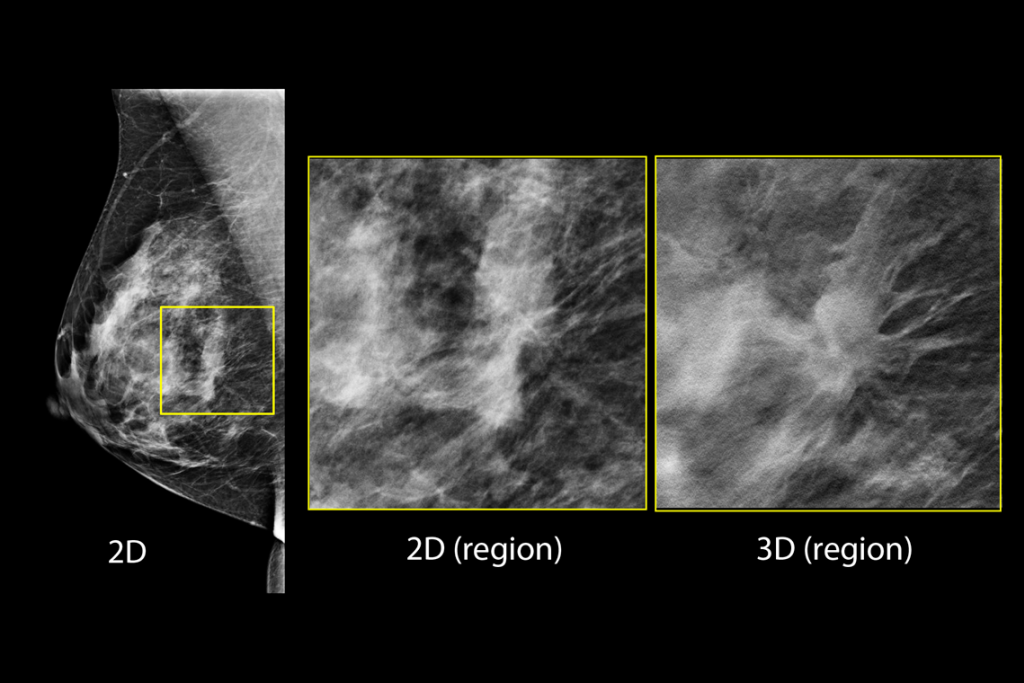

Imágenes clínicas de una mamografía

Imágenes clínicas de una mamografía con una lesión sospechosa